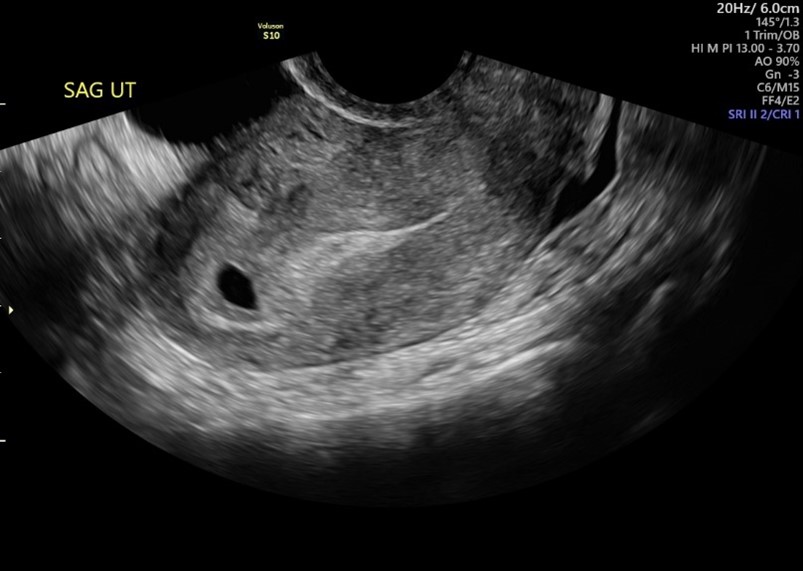

Kết quả siêu âm: Chỉ thấy túi ối (Gestational Sac)

Hình ảnh siêu âm chỉ ghi nhận một túi ối trống, chưa có túi noãn hoàng (yolk sac) và chưa có phôi thai.

Nếu túi ối có kích thước nhỏ (ví dụ, dưới 10mm), đây có thể là dấu hiệu thai còn quá sớm. Tuy nhiên, nếu túi ối có kích thước lớn (ví dụ, 10mm, 15mm hoặc hơn) mà vẫn chưa có phôi, đây là dấu hiệu cần theo dõi sát. Theo Bệnh viện Đa khoa Quốc tế Vinmec, túi thai 10mm tương đương thai 5-6 tuần, và việc chưa có phôi ở thời điểm này vẫn cần được theo dõi thêm.

Kết quả siêu âm: Thấy túi noãn hoàng nhưng không có phôi

Hình ảnh siêu âm ghi nhận túi ối và túi noãn hoàng (yolk sac) nhưng vẫn chưa thấy phôi thai.

Đây thường được xem là một dấu hiệu tích cực hơn so với việc chỉ thấy túi ối trống. Sự xuất hiện của túi noãn hoàng xác nhận đây là một thai kỳ thật sự trong tử cung (loại trừ túi thai giả) và thai đang phát triển đến giai đoạn tiếp theo. Tuy nhiên, vẫn cần siêu âm lặp lại để xác nhận phôi thai và tim thai sẽ xuất hiện sau đó.